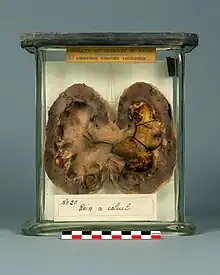

La lithiase urinaire (du grec lithos, pierre) est une maladie caractérisée par la formation de calculs (du latin calculus, caillou), c’est-à-dire des accrétions cristallines qui se forment, à partir de minéraux dissous dans l'urine, dans les voies urinaires : cavités rénales (calices et bassinet), uretères et vessie.

La taille des calculs varie d'un grain de sable à celle d'une balle de golf. Les plus gros, dits « coralliformes », moulent l'intérieur du rein, ayant ainsi l'aspect de branches de corail. Les calculs sont généralement évacués par miction.

Types

La nature de ces calculs est très variable et reflète les mécanismes à l'œuvre dans leur formation[24]. Selon la classification de Daudon, on distingue 7 grands types de calculs définis selon leur composition cristalline. Ces différents types ne sont pas exclusifs l'un de l'autre au sein d'un même calcul : en effet, si certains calculs ne sont constitués que d'un seul type et sont donc dits "purs", la plupart sont un mélange de plusieurs types et sont donc dits "mixtes". Ces 7 types sont les suivants :

Les calculs oxalocalciques (types I et II) sont de loin les plus fréquents à l'heure actuelle dans les pays à mode de vie occidental, représentant environ 80 % du total. Ils sont dans 9 cas sur 10 dus à des erreurs alimentaires, et dans 1 cas sur 10 secondaires à une maladie sous-jacente. Quelle que soit la cause (erreurs alimentaire ou maladie sous-jacente), il en résulte un excès d'oxalate et/ou de calcium dans les urines. Lorsque l'excès urinaire porte préférentiellement sur l'oxalate, ce sont des calculs de whewellite (type I) qui se forment. Lorsque à l'inverse l'excès urinaire porte surtout sur le calcium, ce sont des calculs de weddellite (type II) qui se forment.

Les calculs uriques (type III) arrivent en deuxième position, représentant environ 15 % du total. Leur principal facteur de risque est l'acidité urinaire (pH urinaire < 5.5), qui favorise la précipitation de l'acide urique dissous dans les urines. La principale cause d'acidification permanente des urines est l'insulinorésistance rénale, c'est-à-dire la résistance du rein aux effets de l'hormone insuline. La résistance à l'insuline est un trait commun observé dans un grand nombre de pathologies de l'abondance comme le diabète, l'obésité abdominale, l'hypertriglycéridémie. Ceci explique que la lithiase urique survienne le plus souvent chez des personnes pléthoriques à l'alimentation très riche et déséquilibrée. Dans la population obèse, il s'agit même du type de calcul le plus fréquent, devant les deux types oxalocalciques réunis.